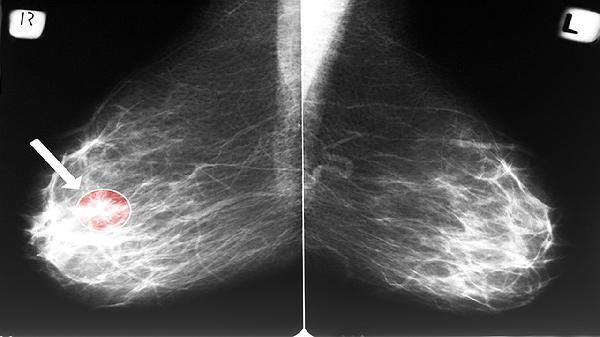

骨巨细胞瘤通常表现为良性肿瘤,好发于20-40岁人群的四肢长骨末端,尤其是股骨远端和胫骨近端。肿瘤生长可能导致骨质破坏,引发持续性钝痛、局部肿胀及活动受限。影像学检查可见偏心性、膨胀性溶骨性病变,边界清晰但无硬化边。病理特征为多核巨细胞均匀分布于单核基质细胞中。手术刮除联合植骨或骨水泥填充是主要治疗方式,术后复发概率较高,需长期随访。